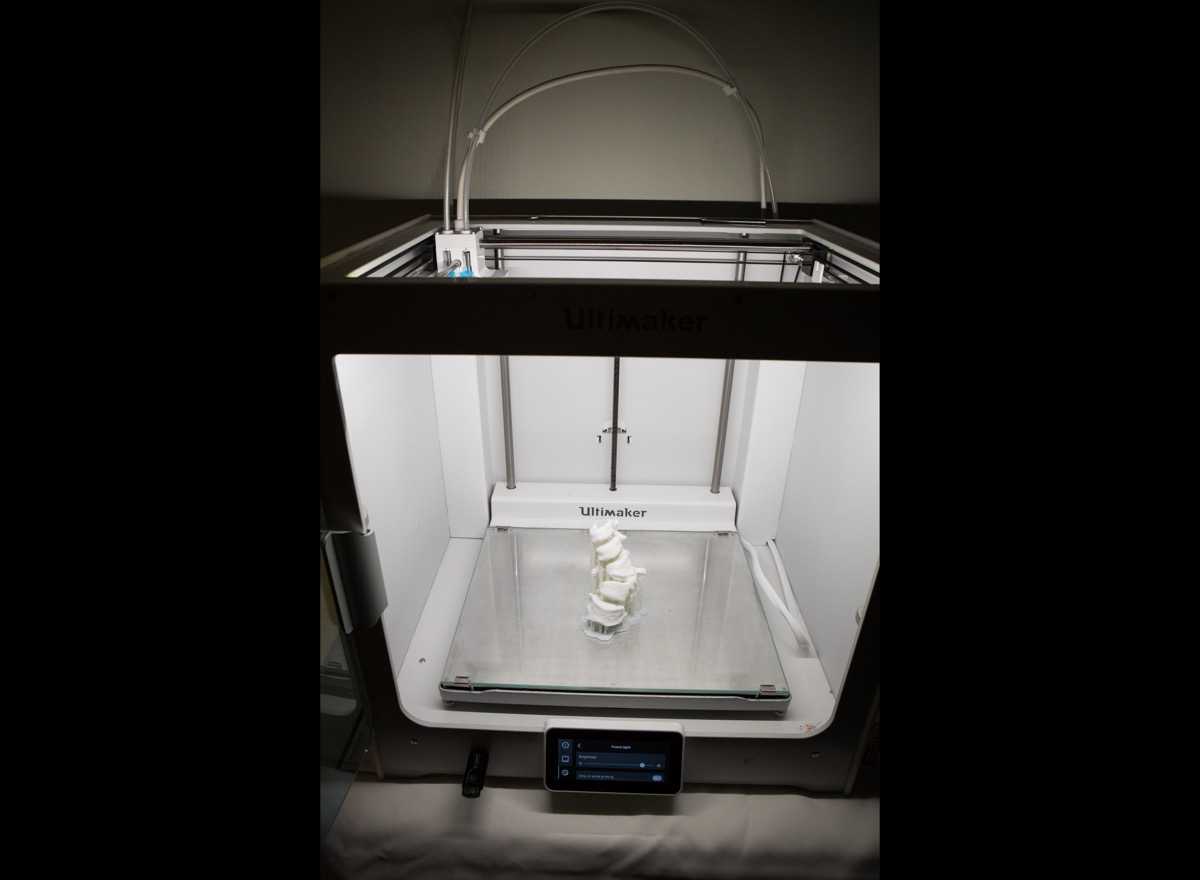

Moses Campus, along with Children’s Hospital at Montefiore Einstein, features 726 adult inpatient beds and 106 pediatric inpatient beds. The facility also offers services to outpatients. As an NCI-Designated Cancer Center, Moses provides diagnostic and therapeutic modalities through an active theranostics program. While training at Moses, residents partake in a particularly rigorous program in oncologic and non-oncologic pediatric and adult nuclear medicine. Our Transplant Center, also on-site, affords residents the ability to evaluate organ physiology pre- and post-transplant.